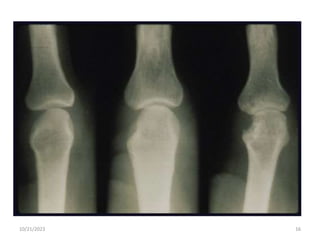

Radiologic findings:

• Soft tissue swelling and osteoporosis near the

joint (periarticular osteoporosis).